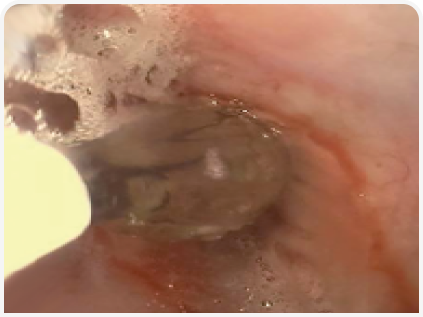

По результатам исследования образцов стенки желудка, полученных методом тонкоигольной аспирационной биопсии под контролем ультразвука, было обнаружено нейтрофильное воспаление. С учетом серьезных подозрений на наличие неоплазии было проведено эндоскопическое исследование желудка. При этом патологических изменений пищевода, дна желудка и большой кривизны обнаружено не было, однако малая кривизна и антральный отдел характеризовались ригидностью и не поддавались расширению при инсуфляции; язвенных поражений не обнаружили. Тяжесть поражений привратника делала невозможным прохождение эндоскопа через пилорус (Рисунок 8).